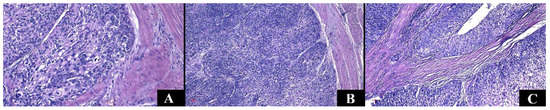

Same Organ, Two Cancers: Complete Analysis of Renal Cell Carcinomas and Upper Tract Urothelial Carcinomas

by Sorin Vamesu, Oana Andreea Ursica, Serban Eduard Milea, Mariana Deacu, Mariana Aschie, Anca Florentina Mitroi, Felix Voinea, Mihaela Butcaru Pundiche, Cristian Ionut Orasanu and Raluca Ioana Voda

Medicina 2024, 60(7), 1126; https://doi.org/10.3390/medicina60071126 - 12 Jul 2024

Cited by 5 | Viewed by 2530

Background and Objectives: Renal cell carcinomas and upper tract urothelial carcinomas are types of malignancies that originate in the kidneys. Each of these examples shows an increasing trend in the frequency and the mortality rate. This study aims to comprehensively define carcinomas by analyzing clinical, paraclinical, and histological aspects to predict aggressiveness and mortality. Materials and Methods: We conducted a retrospective investigation on a group of patients suspected of kidney cancers. Results: We identified 188 cases. We observed a higher mortality rate and older age in individuals with urothelial carcinomas. Anemia, acute kidney injury, hematuria, and perineural invasion were the main risk factors that predicted their mortality. Tumor size in renal cell carcinomas correlates with the presence of necrosis and sarcomatoid areas. Factors that indicate a higher rate of death are older age, exceeding the renal capsule, a lesion that includes the entire kidney, lymphovascular invasion, acute kidney injury, and anemia. Conclusions: Even if they originate at the renal level, and the clinical–paraclinical picture is similar, the histopathological characteristics make the difference. In addition, to these are added the previously mentioned common parameters that can represent important prognostic factors. In conclusion, the characteristics commonly identified in one type of cancer may act as risk factors for the other tumor. The detected data include threshold values and risk factors, making a significant contribution to the existing literature. Full article